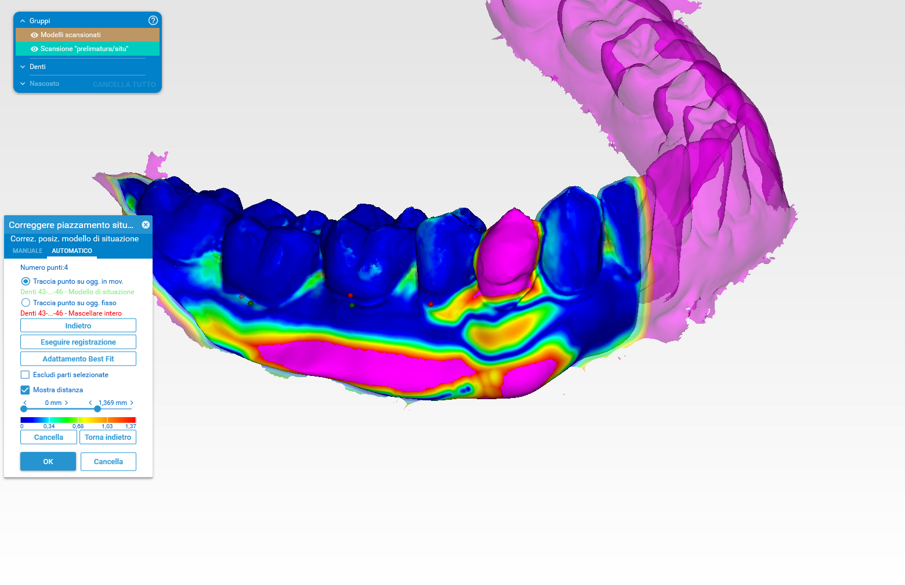

Attraverso l’analisi visiva colorimetrica si è potuto valutare l’incremento volumetrico ai differenti time-points: gli STL ottenuti sono stati analizzati con il software Rhinocerus per l’analisi delle variazioni numerico-volumetriche vestibolari. I dati sono ancora in fase di analisi e in questa parte dello studio è stata presa in considerazione solo l’analisi colorimetrica in un range compreso tra 0 e 2 mm8.

Il gruppo di confronto S0 con S1 (Fig. 11) presenta un aumento lineare che si attesta nell’intervallo tra 0 e 2 mm con zone all’interno dell’area di interesse di colore verde-arancio-rosso. Tale risultato è presente in tutti e 10 i casi analizzati. Nel gruppo di confronto S0 con S2 a distanza di un anno (Fig. 12), vi è un rimodellamento della zona innestata ma con un aumento rispetto la baseline (S0) compresa tra 0 e 1,5 mm, ovvero con zone all’interno delle aree di interesse di colore blu-azzurro-verde. Tale risultato è presente in tutti e 10 i casi analizzati.

L’analisi dei risultati si è basata sulla scala colori con intervallo compreso da 0 a 1,885 mm rispettivamente con scala colori da blu a rosso (Fig. 12).

Questi risultati sono allineati con quanto riscontrato da Huber et al. e Thoma et al. che dimostrano come i sostituti collagenici possono, se correttamente stabilizzati, non solo incrementare la zona d’interesse ma anche essere stabili nel tempo6, 9-11. È interessante analizzare come nei primi tre mesi vi sia un incremento volumetrico importante che poi tende a rimodellarsi per poi diventare stabile a un anno. La valutazione del gruppo S0-S1 infatti evidenzia come in effetti vi sia un aumento maggiore della zona d’interesse arrivando a picchi di colorazione rossa (circa 2 mm).

Analizzando le stesse scansioni, nel gruppo di confronto S0-S2 si evidenzia come vi sia un leggero decremento che a 1 anno si stabilizza in un range che ha portato a un buon aumento medio intorno a 1,00 - 1,50 mm. Thoma et al. dimostrano come sia vantaggioso, per proteggere l’osso peri-implantare, l’innesto di tessuto molle per diminuire la perdita di osso marginale e per creare una zona di tessuto cheratinizzato spesso in grado di proteggere la zona di connessione implantoprotesica10,11. L’innesto di tessuti molli richiede, oltre a conoscenze di chirurgia mucogengivale, l’utilizzo di un sito per il prelievo che può risultare un limite per l’accettazione del piano di trattamento da parte del paziente10.